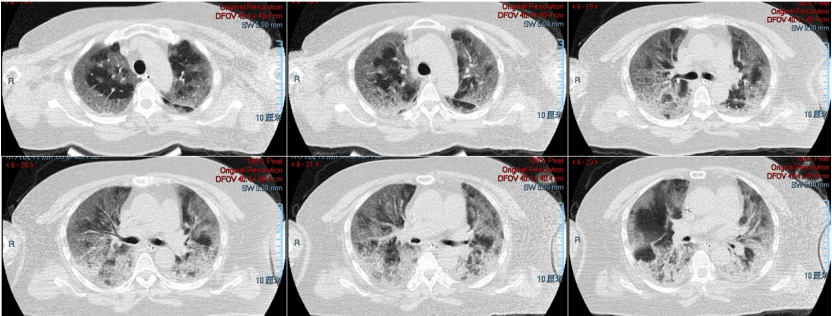

58岁女性患者,高血压、慢性支气管炎病史,发热伴咳嗽9 d,加重2 d,2022年12月19日入ICU(D9)。12月13日新冠抗原(+),12月17日新冠核酸(+)。入院后给予经口气管插管及机械通气,PEEP 12 cmH2O,FiO1.0,俯卧位通气。血气分析:pH 7.396,PaCO2 38.5 mmHg,PaO2 68.9 mmHg,同时予以其他脏器支持,去甲肾上腺素维持血压。下图为患者发病第8天的胸部CT。

患者2022年12月18日胸部CT